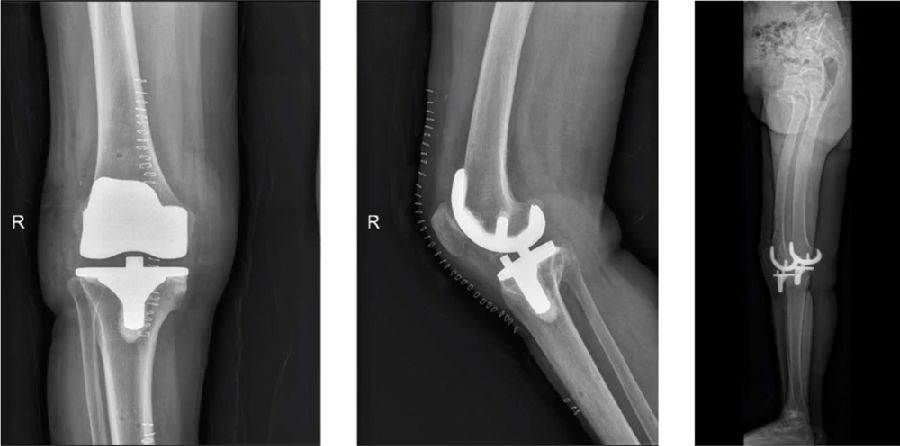

图15 术后影像(R)